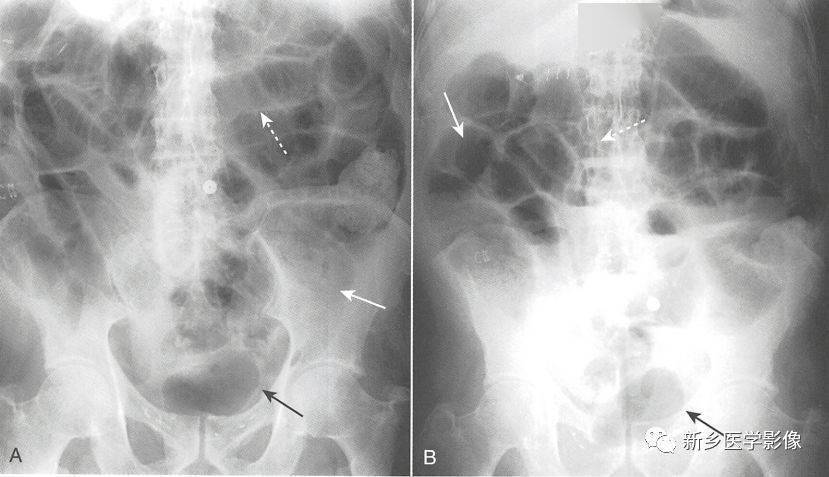

如何辨识肠梗阻

x 线片多可发现肠腔充气扩张或低位肠梗阻,造影显示典型的狭窄段,扩张

详细肠梗阻的分类及影像学表现高清图片文字讲解

小肠梗阻 特点:气液平面.

高清图片文字讲解肠梗阻的分类及影像学表现

肠梗阻腹部平片